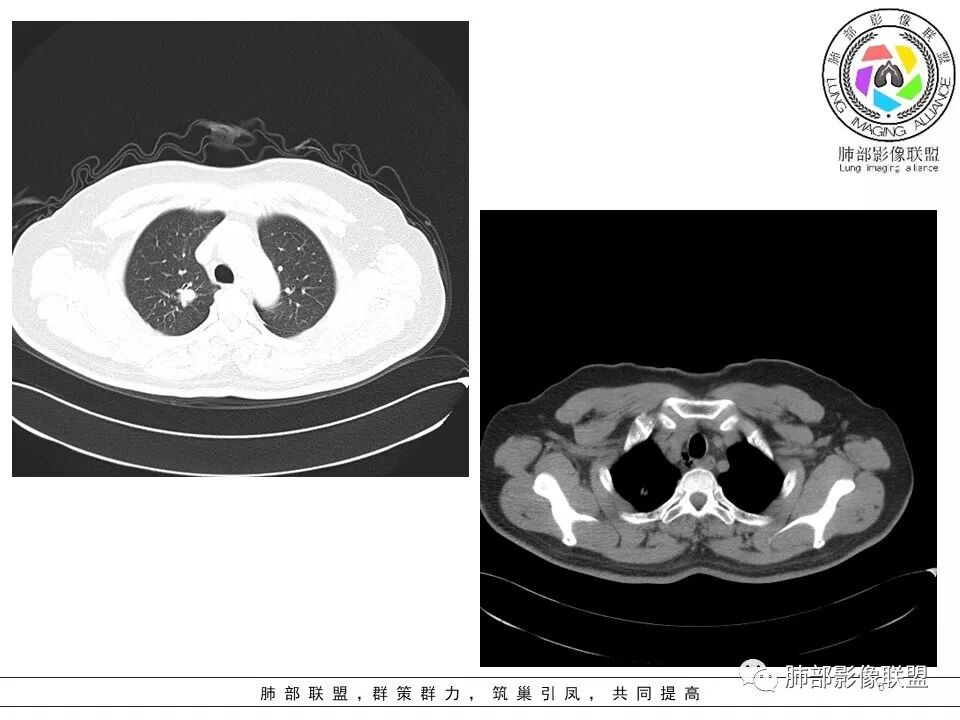

患者中年男性,主诉:咳嗽  胸痛。  胸CT:右肺上叶尖段占位,病灶位于支气管外,病灶周围部分区域可见毛玻璃影,病灶边缘不规则,部分区域可见平直,胸膜牵拉(无胸膜凹陷),柔软长毛刺,分叶,纵隔窗病灶没可见低密度区,左肺尖可见一点状病灶,病灶整体考虑良性疾病:感染性病变(结核?),感染后机化?。恶性病变待除外。

晨读:患者中年男性,反复咳嗽1月余,伴左胸部疼痛1周就诊。胸部CT:右肺上叶尖后段不规则结节,见长毛刺、胸膜牵拉、条索影,周围见卫星灶。未见明显淋巴结肿大,符合结核病变。鉴别其他。但其病灶位于右肺,主诉左胸痛,是误写,还是?

小飞:  晨读:右肺上叶不规则结节灶,沿支气管走形分布,边缘平直,U型凹陷,脊柱侧有少许磨玻璃影,左肺尖少许斑点灶,综合考虑结核。

影像,气管憩室,两肺尖都有病灶,长索条

遗憾的是:层厚太厚,无重建